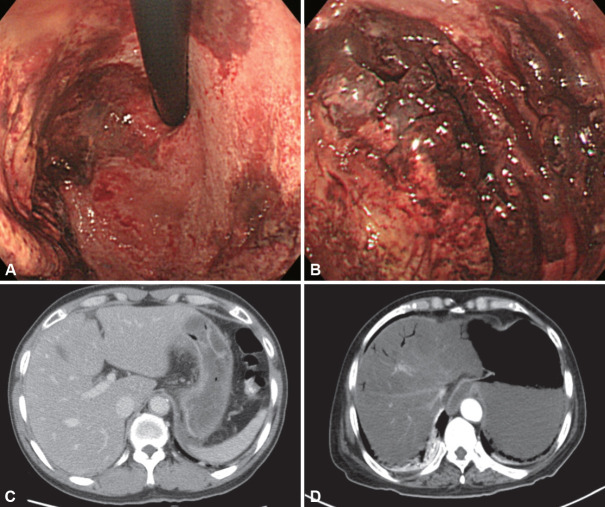

Gastric ulcers are characterized by mucosal damage extending into the submucosa or deeper, with the most common causes being Helicobacter pylori infection and nonsteroidal anti-inflammatory drug use. However, various infectious pathogens, such as pyogenic bacteria, Treponema pallidum, Mycobacterium tuberculosis, viruses, fungi, and parasites, can also cause gastric ulcers. Non-H. pylori infectious gastric ulcers are uncommon and often present with nonspecific symptoms, making their diagnosis challenging. A differential diagnosis requires a comprehensive understanding of the underlying diseases and familiarity with their characteristic endoscopic features. For instance, acute phlegmonous gastritis requires a prompt diagnosis based on typical clinical symptoms and abdominal computed tomography findings, followed by empiric antibiotic therapy. Infections such as gastric syphilis, gastric tuberculosis, cytomegalovirus (CMV) gastritis, and gastric candidiasis necessitate pathogen identification through tissue diagnoses. When this is challenging, the clinical history, endoscopic findings, and serological tests should be integrated to ensure an accurate diagnosis and management. Unlike gastric syphilis and tuberculosis, CMV gastritis and gastric candidiasis often occur secondary to preexisting gastric ulcers; therefore, conventional anti-ulcer therapy is sufficient for immunocompetent patients with mild symptoms. However, antiviral or antifungal agents should be administered to immunocompromised patients and to those with systemic symptoms related to the infection. Similarly, understanding the characteristic history and symptoms of gastric anisakidosis is crucial for an accurate diagnosis, and prompt endoscopic examination is essential to identify and remove the larvae. Clinicians should consider the possibility of infectious gastric ulcers in patients with atypical ulcerative lesions or ulcers that are unresponsive to conventional therapies. Accurate diagnoses and timely treatments are essential for improving patient outcomes.